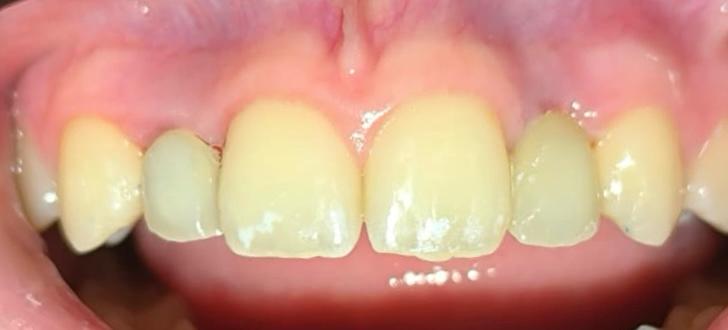

Resultados inmediatos y estética natural.

Lo que realmente nos diferencia es la carga inmediata. No queremos que salgas de nuestra clínica con un hueco en tu sonrisa. En el mismo momento de la cirugía, preparamos coronas provisionales que no solo devuelven la estética, sino que ayudan a que tu encía se cure con la forma perfecta.

El éxito de este caso, que terminó con una paciente feliz y una sonrisa renovada, no es fruto del azar. Es el resultado de combinar la dilatada experiencia del Dr. Dario Castro con la tecnología de Microdent y una visión centrada en la comodidad del paciente.